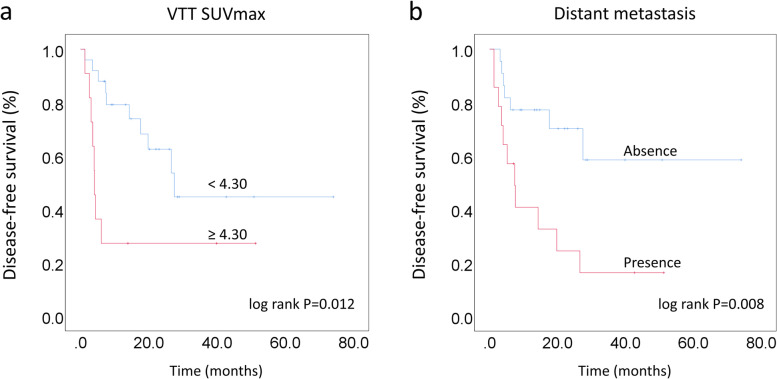

Considering the differences in prognosis of various histological subtypes [21–23], only ccRCC patients with VTT were enrolled in prognostic analysis. As determined by ROC curves, the cutoff value of primary tumor SUVmax to predict DFS was 4.45, with a sensitivity of 77.8% and specificity of 55.6%, and that of VTT SUVmax was 4.30, with a sensitivity of 44.4% and specificity of 83.3%. The cutoff value for primary tumor size was 8.65 cm determined by median. The results of univariate and multivariate Cox proportional hazards analysis are shown in Table 5.

Elevated VTT SUVmax (P = 0.018, HR 3.123, 95% CI 1.212–8.044) and distant metastasis (P = 0.013, HR 3.344, 95% CI 1.293–8.649) from 18F-FDG PET/CT were found to be independent predictors for DFS. Kaplan-Meier survival curves showed that in ccRCC patients with VTT, those accompanied with elevated VTT SUVmax (≥4.30) (P = 0.012) and distant metastasis (P = 0.008) had more unfavorable DFS than their counterparts (Fig. 4). The typical cases are shown in Fig. 5.

Fig. 4.

Kaplan-Meier survival curves analyses for DFS between the groups categorized according to VTT SUVmax (a) and distant metastasis (b)